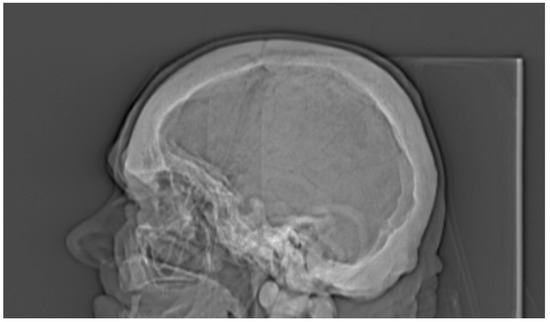

3. Results